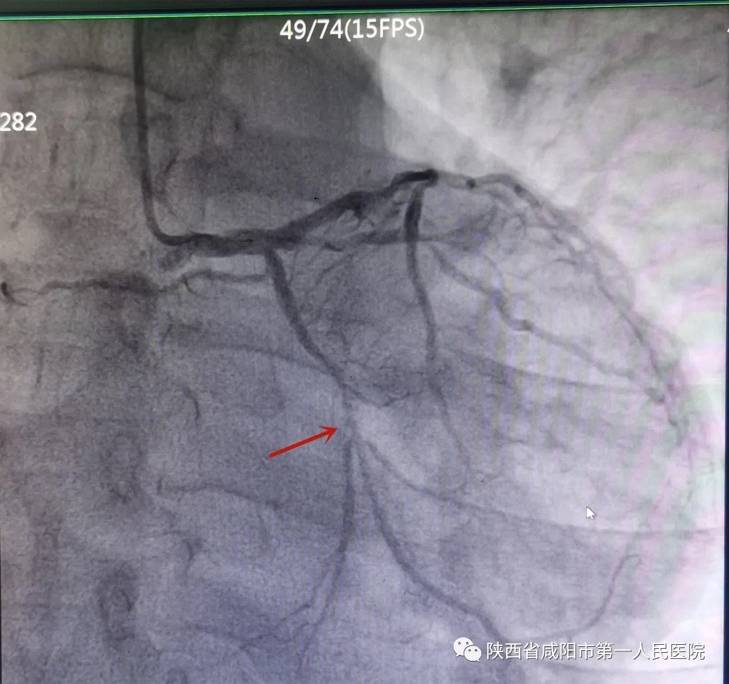

心血管病院院长张宏考接诊后 , 为他做了详细检查 , 发现他的心脏问题非常严重, 面临“双重困境” , 不仅有冠心病 , 同时二尖瓣关闭不全 。 冠脉造影提示患者右冠、前降支等多支血管狭窄75%以上 。 而这些是心脏的主要供血血管 , 如今严重狭窄 , 心肌细胞严重受损 , 若不及时救治 , 随时有猝死的危险!